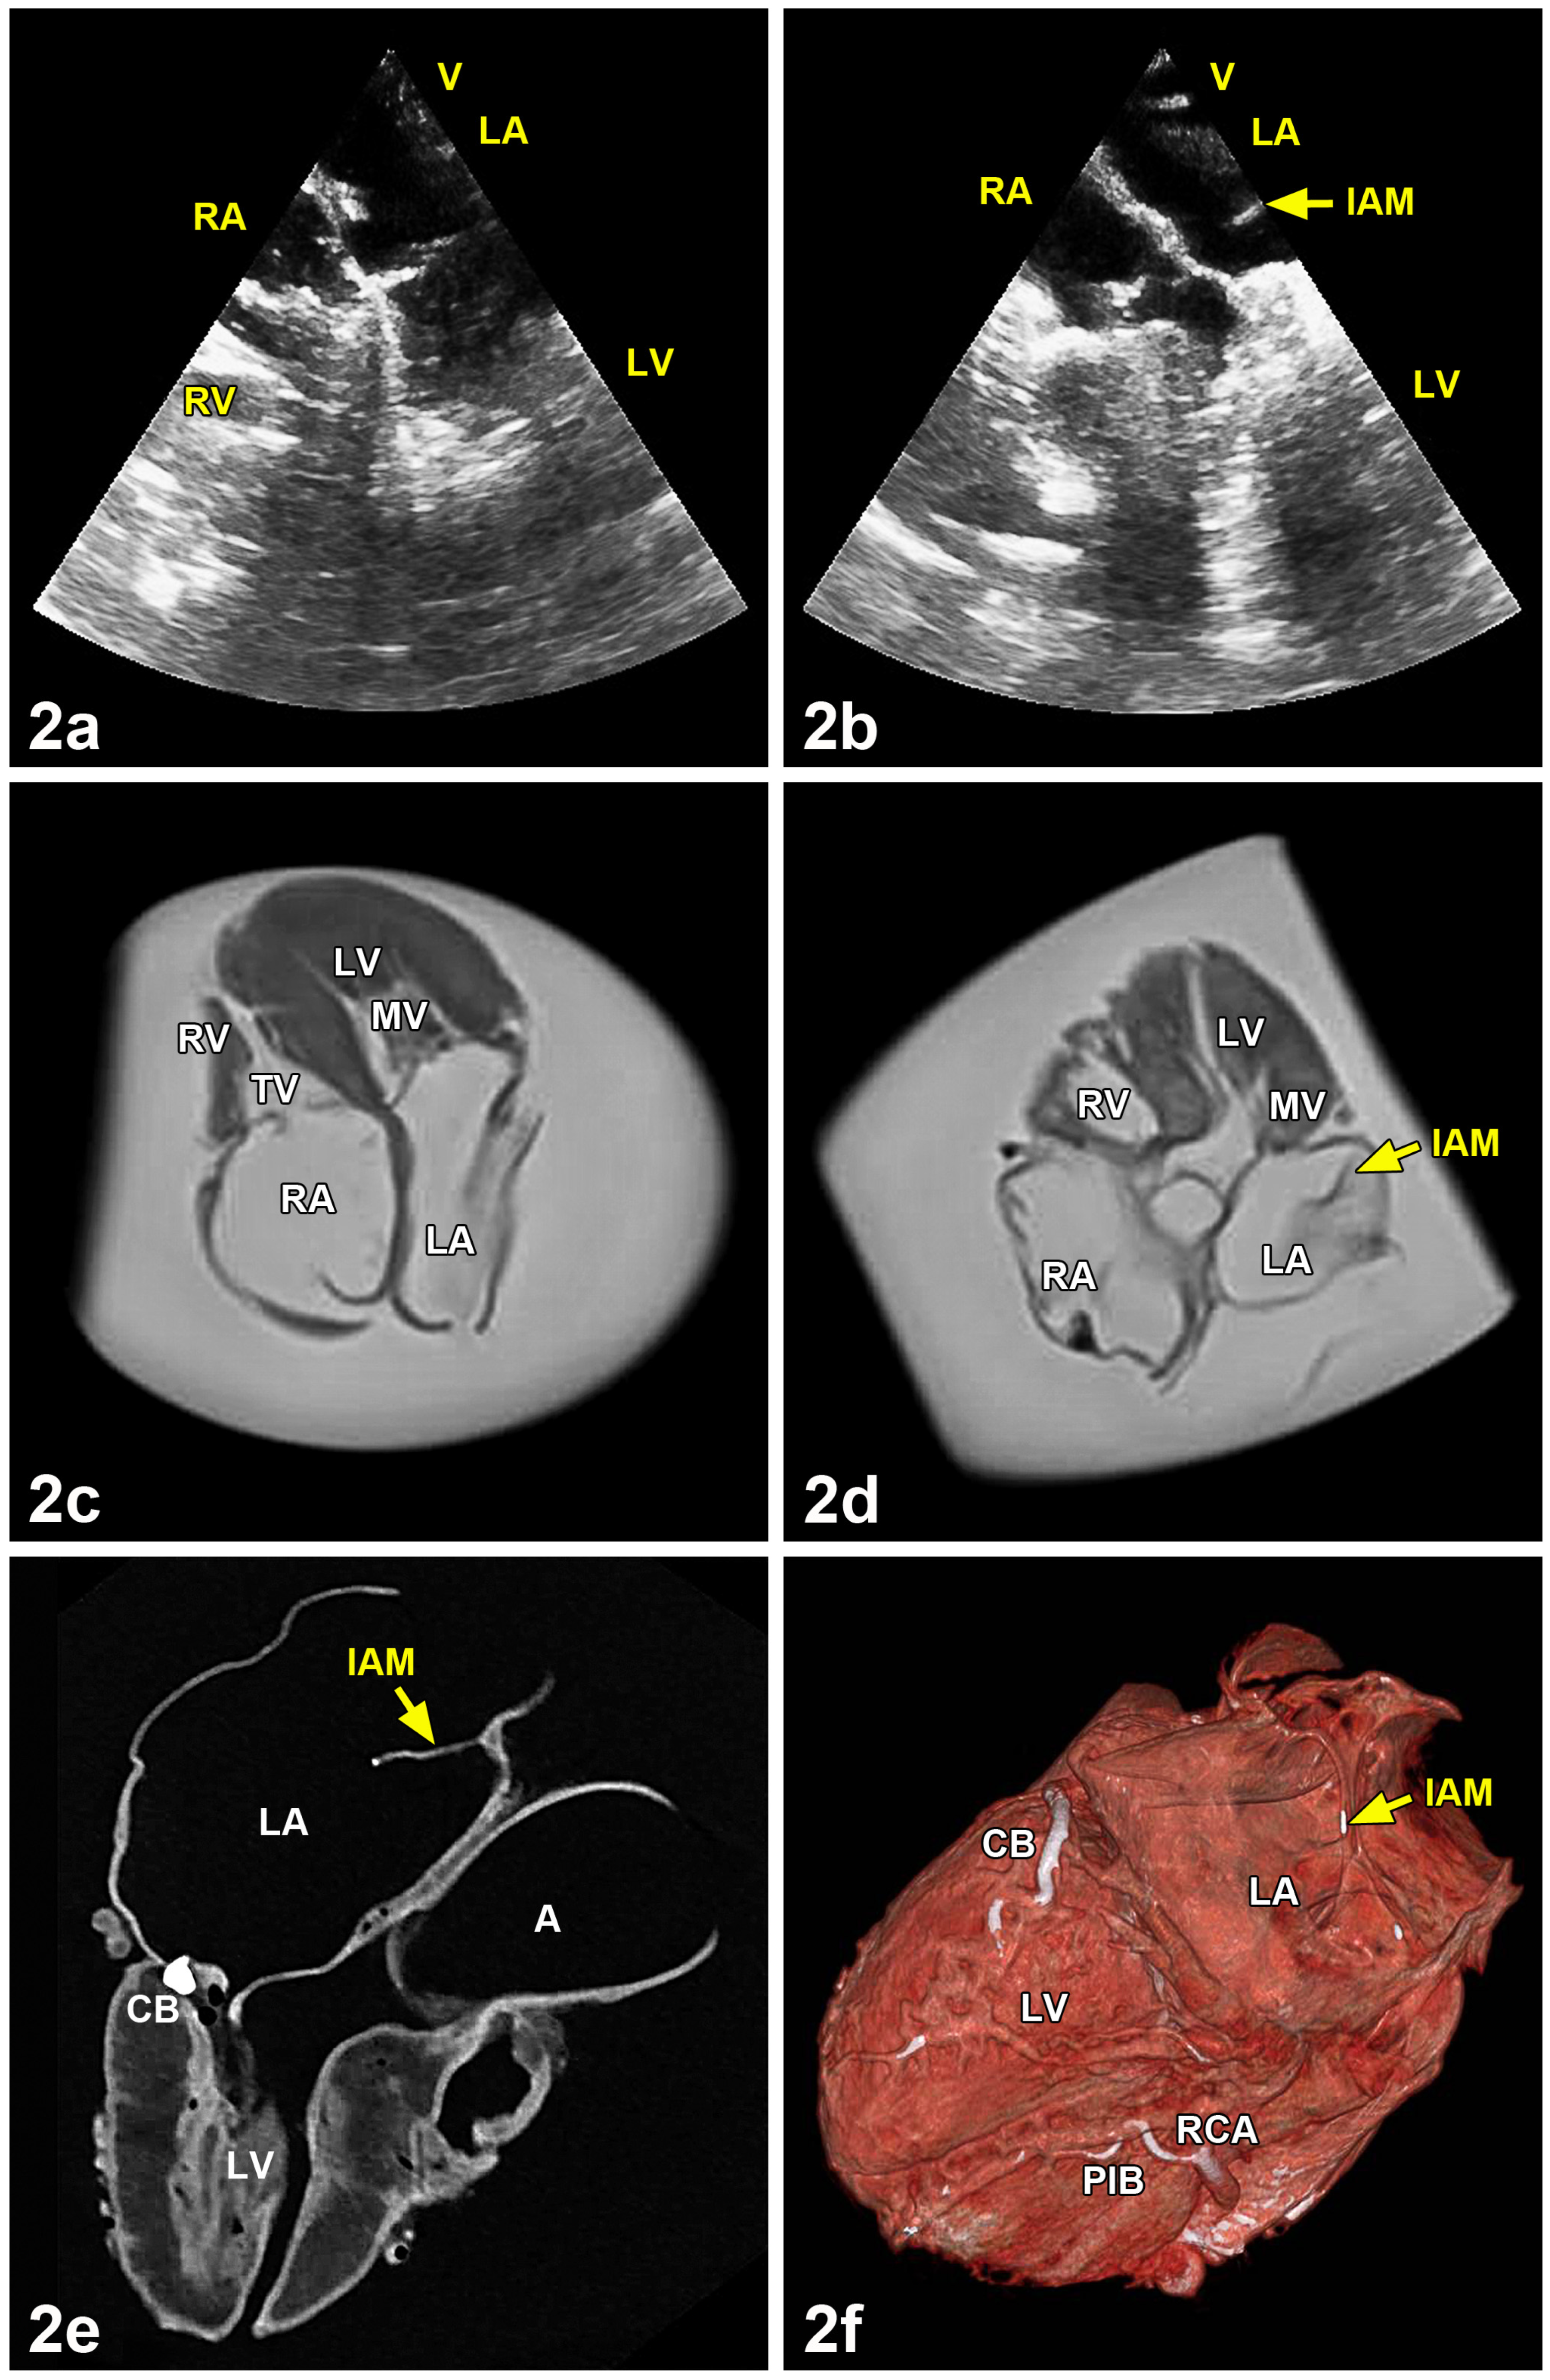

2. Materials and Methods

3.3. Analysis by Ultrasound, Magnetic Resonance Imaging, Computed Tomography and Cinematic Rendering